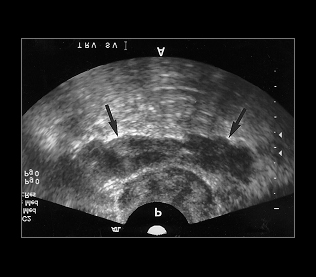

5. 전립선 초음파검사

전립선 초음파검사는 항문을 통해 초음파 기구를 삽입하여 전립선의 크기와 이상을 평가하는 검사로서, 주변 정낭의 이상 여부까지 판단할 수 있습니다. 필요한 경우 조직검사를 위해 초음파로 전립선을 직접 시각화할 수 있습니다.